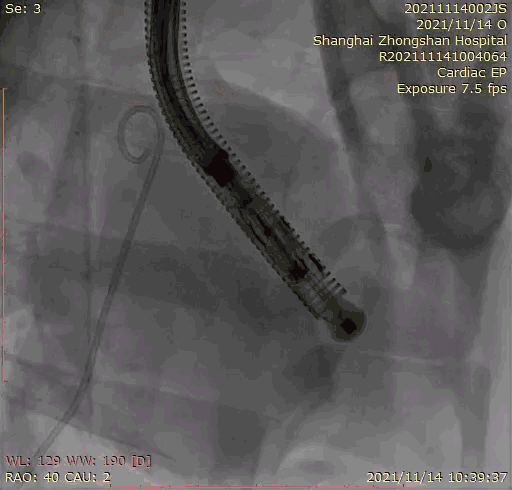

本次临床前研究经右侧颈静脉置入LuX-Valve Plus输送系统可调弯鞘管,在DSA及超声引导下将人工三尖瓣瓣膜植入到原有三尖瓣位置,利用独特的锚定技术将人工瓣膜支架可靠固定在预定的位置。

上海中山医院葛均波院士、钱菊英院长、周达新教授、潘文志教授、潘翠珍教授、李伟教授共同完成此次临床前研究。术后葛均波院士对Lux-Valve Plus的器械操作性能给予了高度评价,DSA和超声影像也显示出在本次研究中Lux-Valve Plus的安全性和有效性俱佳。